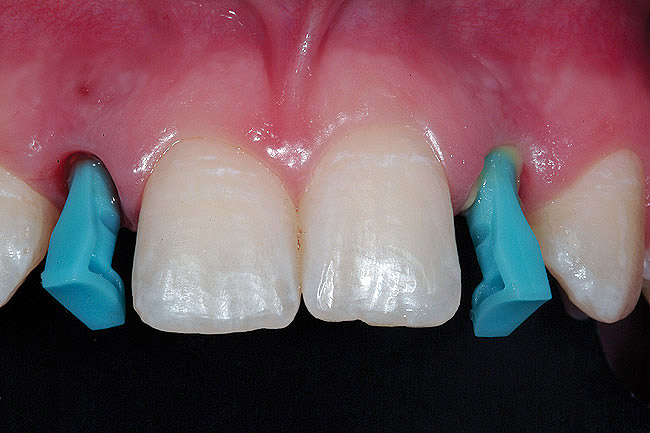

Figure 4  Pretreatment clinical view, right lateral incisor.

Figure 4

Figure 5  Pretreatment clinical view, left lateral incisor.

Figure 5

A 19-year-old non-smoking female presented for tooth replacement at the maxillary right and left lateral incisors, which were congenitally missing (Figure 1). The post-orthodontic result was adequate for the placement of 3-mm one-piece small-diameter implants. The preoperative radiographs can be seen in Figure 2 and Figure 3. The pretreatment clinical view in Figure 4 and Figure 5 shows the small intertooth space present in the lateral incisor areas. One of the most challenging tasks with congenitally missing lateral incisor cases is to create an acceptable soft tissue emergence profile from a crestal profile that is flat from the mesial of the canines to the distal of the centrals (Figure 4 and Figure 5). After pretreatment planning which consisted of a complete medical and dental history, radiographic analysis, and upper and lower study models mounted by a facebow transfer technique, the fabrication of a TempStent II surgical guide was completed. Figure 6 and Figure 7 show the occlusal view of the TempStent II guide on the study cast and in the oral cavity, respectively.